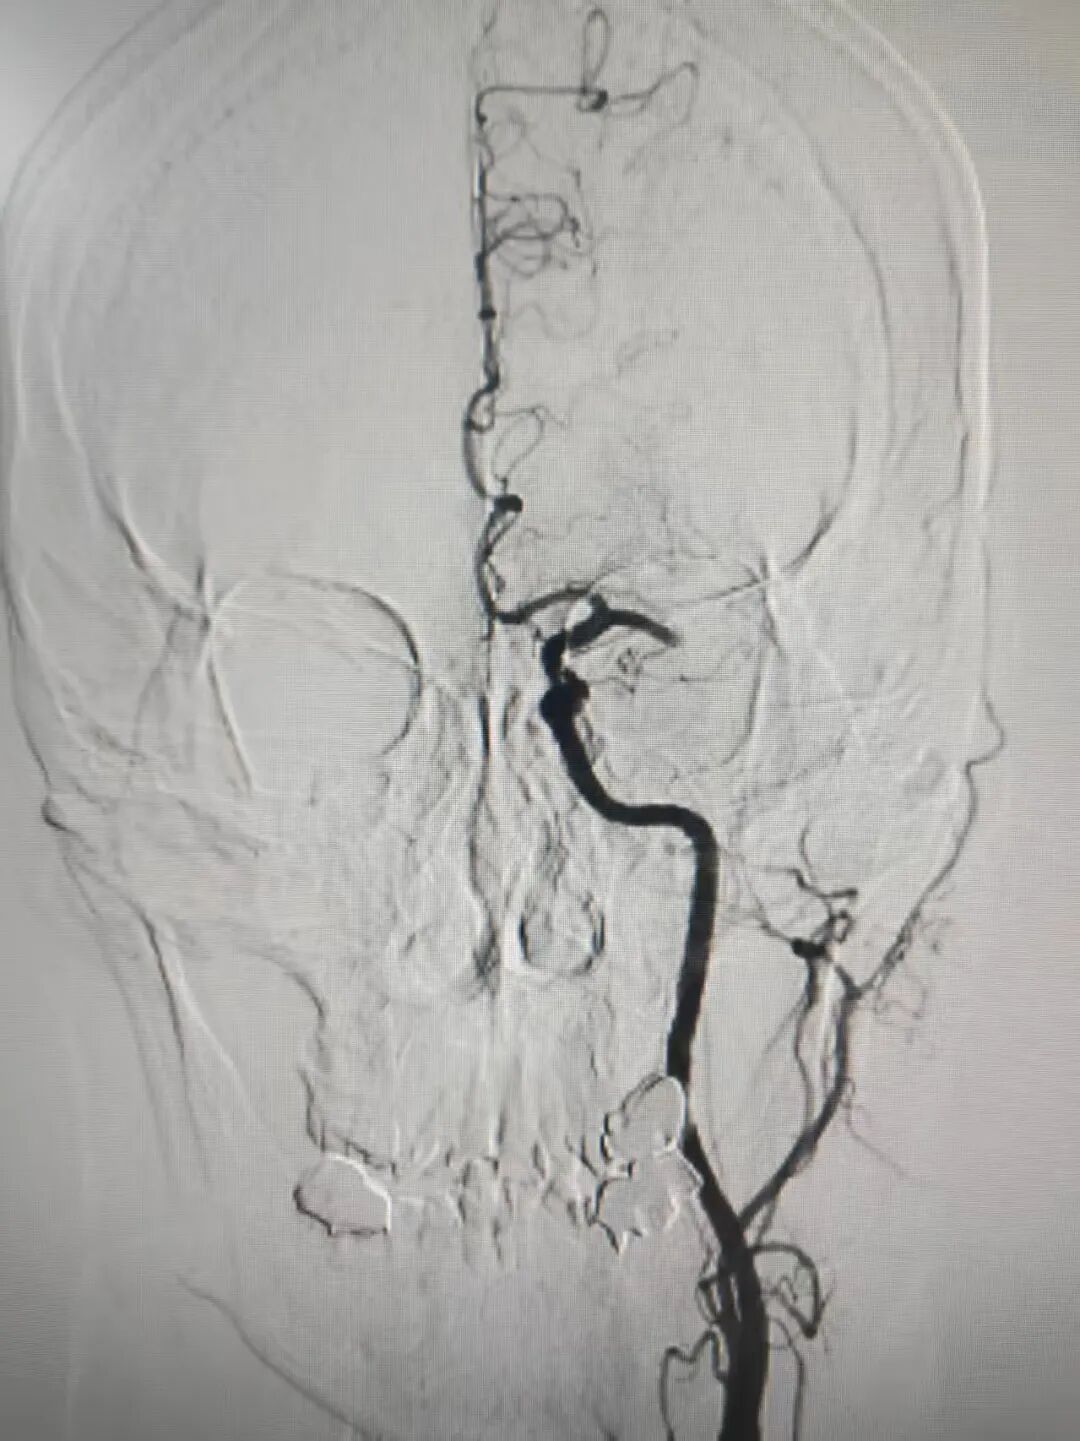

时间就是大脑!神经内科介入团队火速行动。19:50,患者被送入介入室,在局部麻醉下,邹永彪主任医师及其介入团队成员为患者立即施行了脑血管造影术,造影结果显示:左侧大脑中动脉闭塞,这是导致患者昏迷及右侧偏瘫的直接原因。团队凭借精湛技术,运用先进的取栓支架系统,精准定位并成功取出堵塞血管的暗红色血栓。术后造影显示,原先闭塞的左侧大脑中动脉及其分支恢复显影,前向血流重建!整个手术过程从穿刺到成功再通,仅用时约1小时。